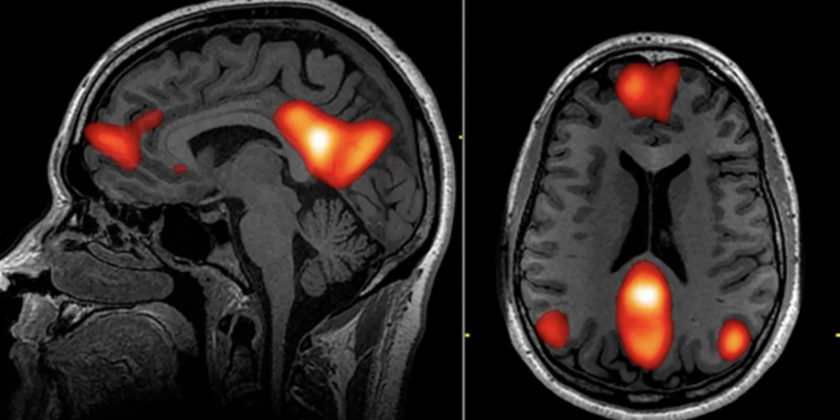

Na przykład, obniżona metylacja niektórych genów związanych z agresją (np. MAOA – gen wojownika) może prowadzić do nadmiernej reaktywności emocjonalnej i zwiększonej impulsywności. Niektóre badania sugerują, że osoby przejawiające przemoc mogą mieć podwyższoną reakcję dopaminową na działania związane z dominacją i agresją – co może sprawiać, że przemoc daje im 'nagrodę’ neurologiczną i utrwala ten wzorzec i może prowadzić do trwałych zmian morfologicznych.